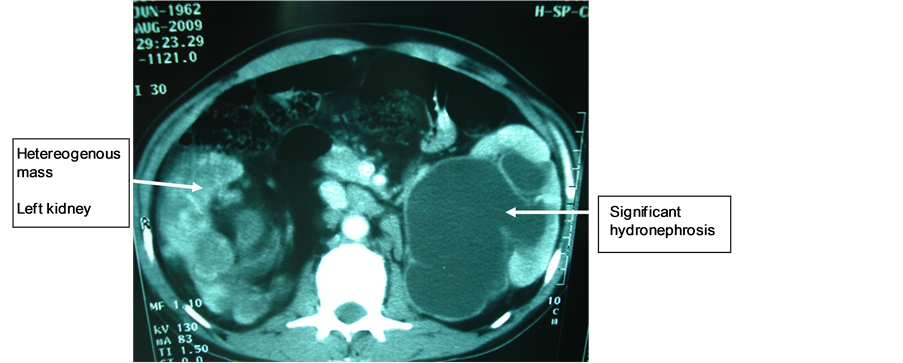

Mr. M.N., 47 years old, with a long history of left lower back pain relieved by usual analgesics, was hospitalized in emergency for lumbago, hematuria, fever at 39˚C and altered general condition. Physical examination revealed hematic urines and a right lumbar fossa sensitivity. Biological and bacteriological laboratory exams revealed a hyperleukocytosis and a Klebsiellapneumoniae infection in urine cultures. The ultrasound showed that the right kidney was enlarged, with highly dilated cavities and heterogeneous content. The CT scan showed an enlarged right kidney, cavities with heterogeneous content (pyonephrosis) and a significant dilatation of the left pyelocaliceal (Figure 4). Right pyonephrosis was diagnosed and a left ureteropelvic junction syndrome was also suggested. Treatment included a left nephrostomy and a right nephrectomy. The macroscopic aspect was in concordance with morphological data, revealing a pyonephrotic kidney and a right pyelocaliceal tumor. The postoperative course was marked by a parietal suppuration on the third day. Histological analysis of the resected specimen indicated that it was a low-grade papillary carcinoma of the urinary tract (PT3G1 stage). Postoperative follow-up showed a recurrence two months later on the remaining ureteral stump by ultrasound, as well as celiac lymph nodes, and spleen and liver metastases. Chest X-ray also revealed lung metastases (Figure 5). The patient died two months after surgery.

Figure 4. Heterogeneous mass on the right kidney and right hydronephrosis.